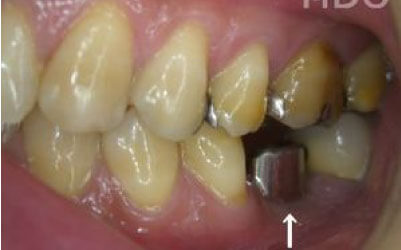

2 歯が傾いてくる、落ちてくる

歯は互いに支え合ってバランスを保っています。つまり、歯が抜けるとその支えがなくなり、抜けた部分の隣の歯が倒れたり、上の歯が下に沈んだりすることがあります。